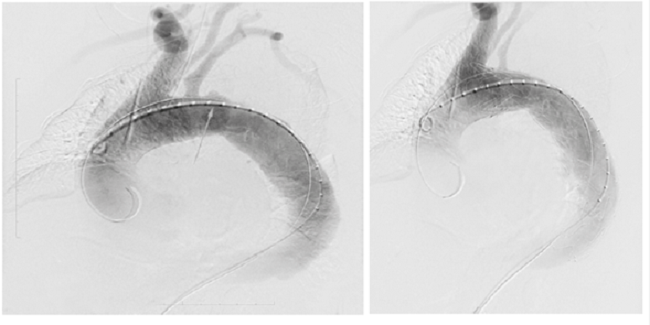

Fue sometida a una corrección endovascular de ruptura aórtica torácica, con endoprótesis recubierta (Medtronic Valiant VAMF2222C 150TE™), la cual se desplegó respetando el orificio de la arteria subclavia izquierda y se logró el cubrimiento exitoso del sitio de ruptura, sin evidencia posterior de extravasación con medio de contraste (figura 2).

Se decidió hacer una corrección endovascular con una endoprótesis aórtica cubierta (Cook Zenith Alpha Thoracic Endovascular Graft™). Fue necesario cubrir el orificio de la arteria subclavia izquierda, lo cual no produjo complicaciones. La evolución fue satisfactoria y se dio de alta tres días después (figura 7).